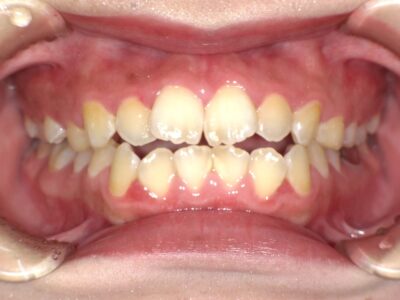

21歳、女性の患者さま。前歯が噛み合わないことに加え、横顔の見た目(口元の突出感)を気にされて来院されました。

診察の結果、前歯が噛み合わない「開咬」に加え、口元が前方に出やすい状態が見られたため、かみ合わせと横顔のバランスの両方を改善できる治療計画をご提案しました。

■治療前後の変化

治療前は前歯にすき間があり、口元の突出感も見られましたが、治療後は前歯がしっかり噛み合い、口元がすっきりとした印象になりました。横顔のバランスも整い、より自然な口元へと変化しています。